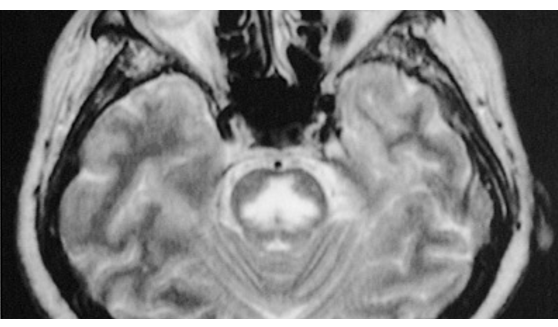

Risk of osmotic demyelination (central pontine myelionlysis)

quadriplegia, dysarthria, dysphagia, seizures, coma, death

Disrupts blood brain barrier, inflammatory cytokines